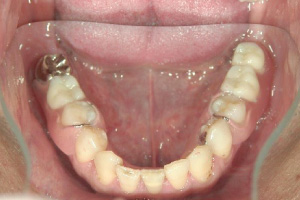

下顎(装着時)

下顎左側

ミラクルデンチャーフィットⅢによる義歯作成

年齢・性別 39歳・男性

治療期間 型取り1回

かみ合わせ採得1回

義歯の試適1回

義歯の完成・装着1回

計4回(2か月程度)

費用 上顎:

108,000円(税込)

下顎:

64,800円(税込)×2

• 主訴、治療計画・内容

「目立たなくて、なるべく違和感の少ない入れ歯を作りたい。」との主訴で治療開始。

義歯の支えとなる歯が虫歯・歯周病になっている為まずそちらの治療を行い、義歯の支えとなる歯を中心としたブラッシング指導を行った後に義歯の型取りを行う。ミラクルデンチャーは保険の義歯とは取り外し・装着が異なる為、練習が必要になる場合がある。